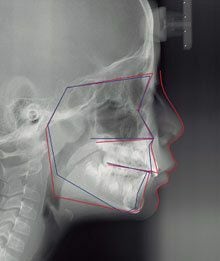

矯正治療を始めるにあたり不可欠な「セファログラム」画像。赤線が患者の顎骨と歯のライン。青線で示した平均的なラインを目安に治療計画を立てる。三村博氏提供